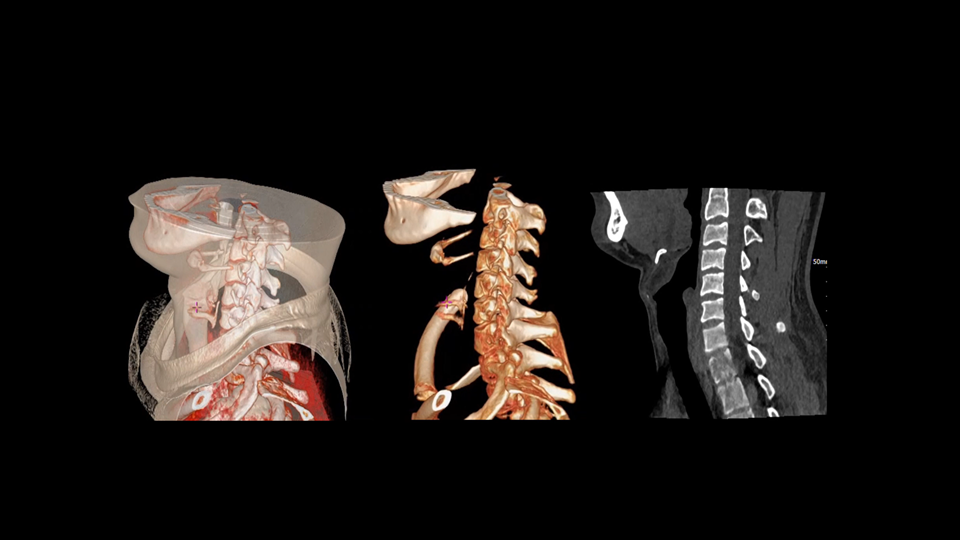

uCT SiriuX® 以16cm超宽Z轴覆盖,使超高时间分辨率应用于完整器官成像。无论是心脏搏动还是关节运动,整个目标区域可在同一瞬时被完整、清晰地捕捉,彻底消除时序误差,实现从“局部瞬间”到“全器官瞬时”的成像跨越。

全器官同步

全身各部位动态CT成像